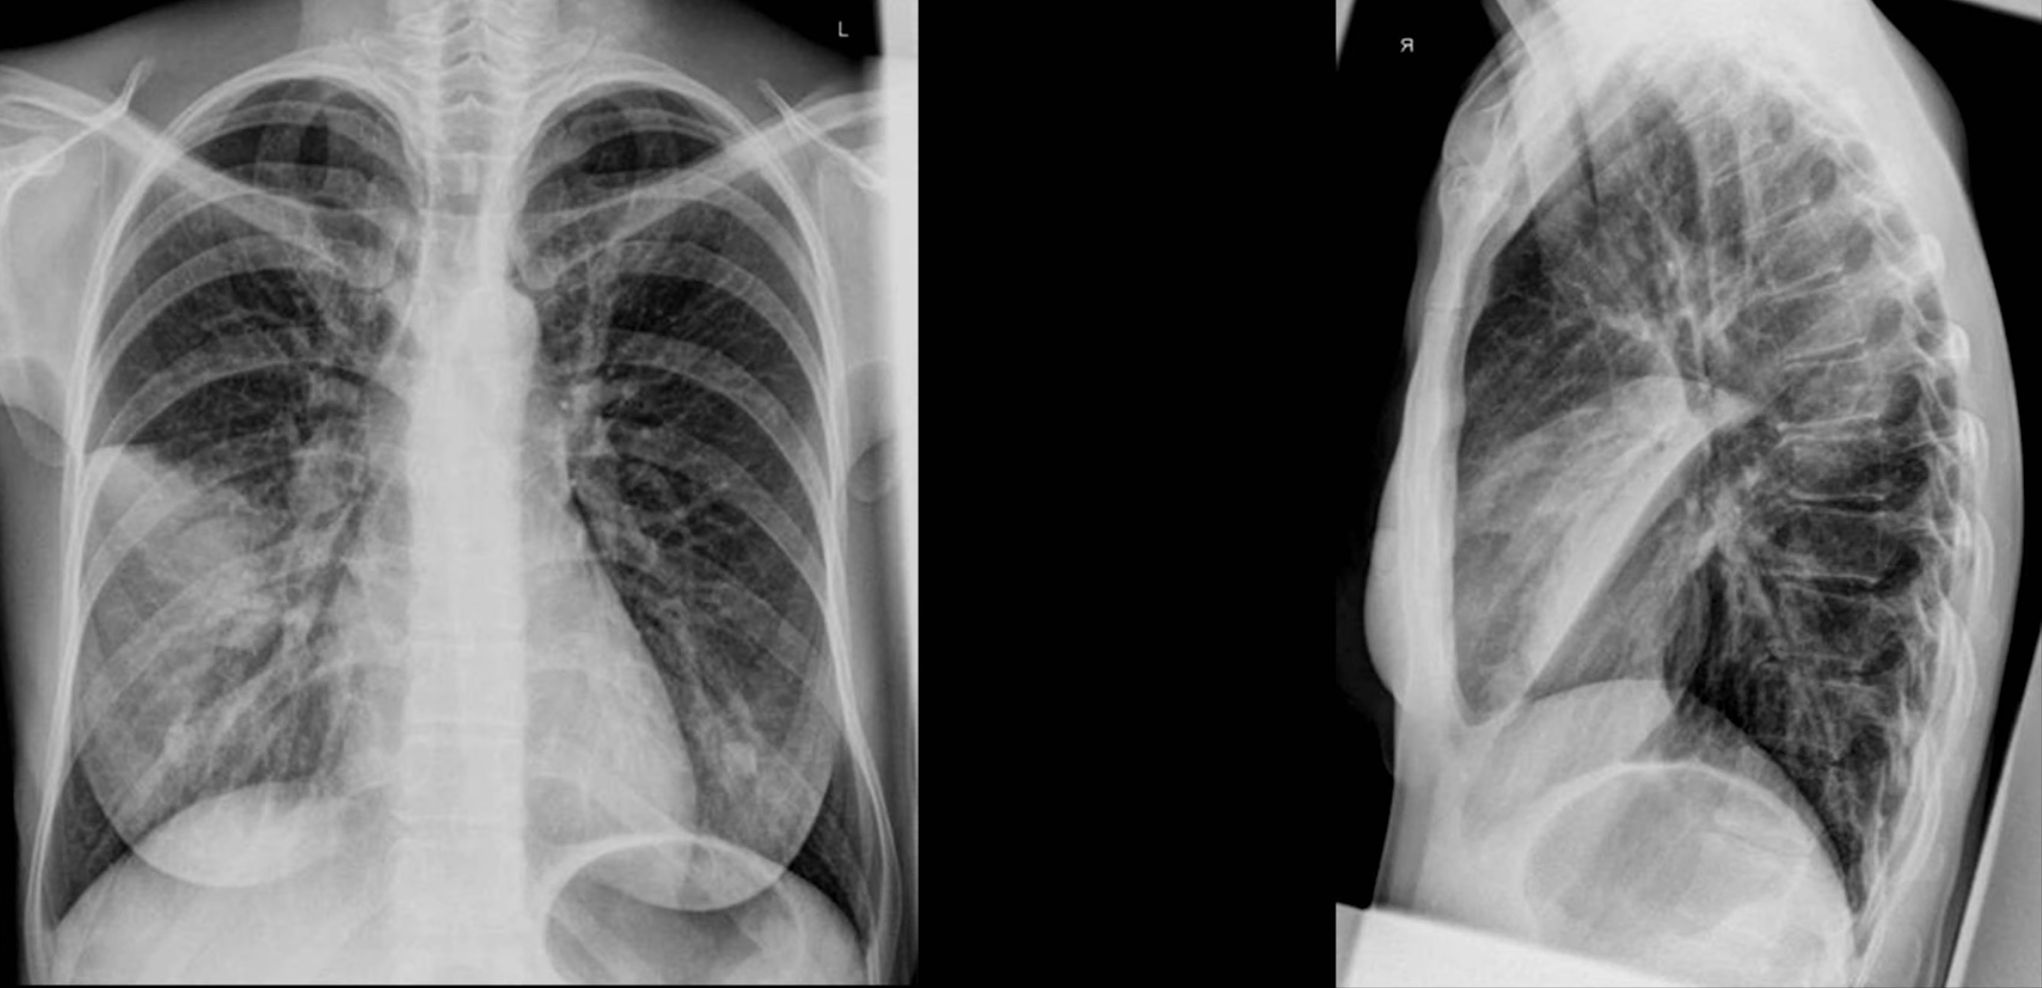

Rotation

Ensure the patient is not crooked (rotated/slumped to one side). Ensure lung apices are visible above the clavicles. Ensure the vertebral spinous processes bisect the distance between the medial ends of the clavicle.

- The spinous processes will be closer to the clavicle on the side that is rotated forward

Penetration

Considered good when the outlines of the vertebral bodies are visible behind the heart (focus on inter-vertebral spaces).